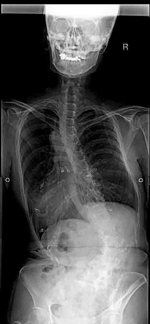

せぼね(脊椎)は7個の頚椎、12個の胸椎、5個の腰椎と仙椎から構成されます。正常な状態では脊椎は正面から見ると真っ直ぐです。一方側弯症では正面から見た時に椎体がねじれ(回旋)を伴いながら、脊椎が左右に曲がっている状態です。側弯症の発生頻度は、装具治療の対象となる20-30度以上の側弯症はおおよそ0.3~0.5%と報告されています。手術が必要な可能性が出てくる40度以上の側弯はおおよそ0.1%です。

側弯症では脊柱が曲がってくるため、以下のような外見状の変化が生じる場合があります。

- 肩の高さの非対称

- 腰のくびれの非対称

- 骨盤の傾き

- 肩甲骨部の背中の出っ張り

特に最も多い胸椎が右に弯曲する側弯症ではアダムステストと呼ばれる体幹を前に屈めるテストを行うと、右の背中が盛り上がります。痛みや機能の障害を伴うことは比較的稀です。